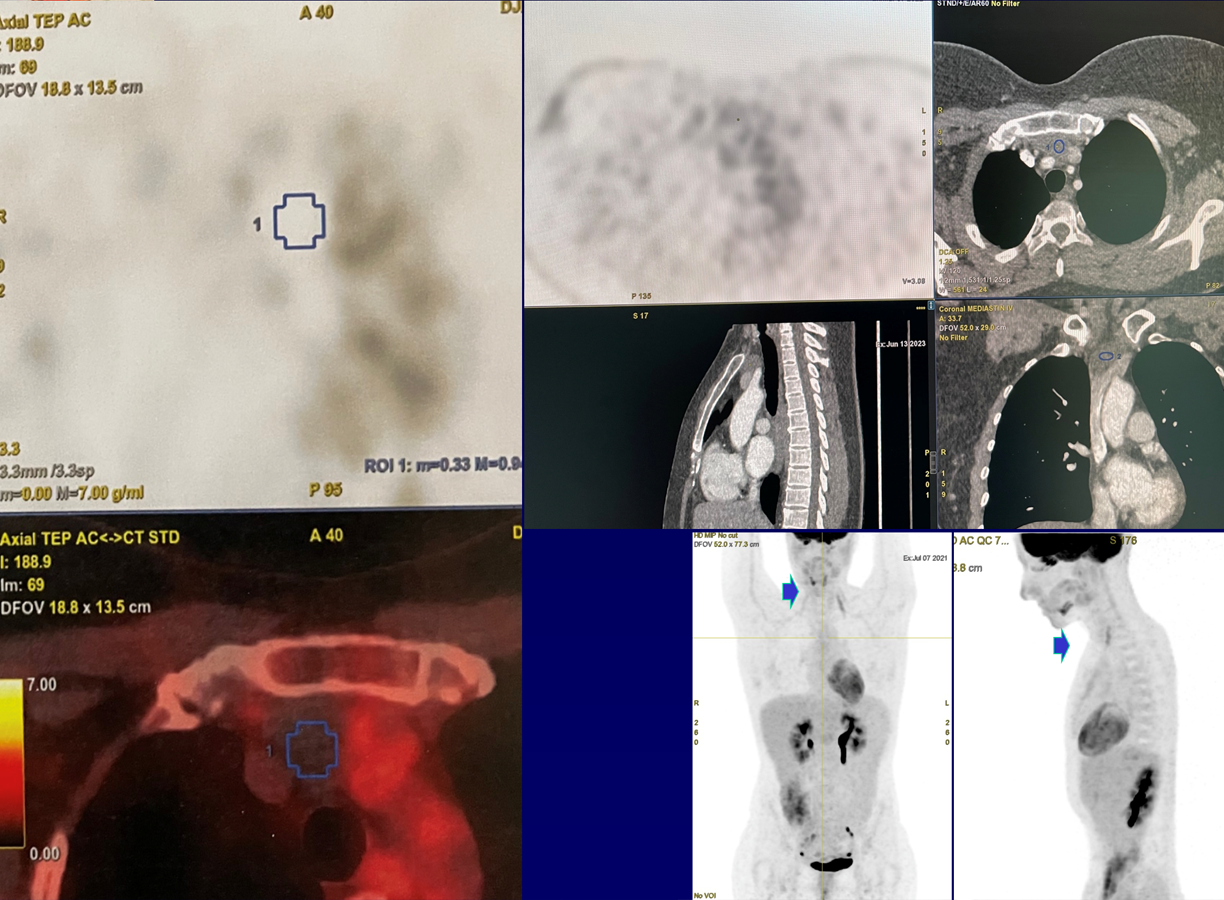

Masse 38 x 21 x 24mm

Parenchyme pulmonaire - pas de nodule - Pas d'épanchement des séreuses - Hépatomégalie homogène